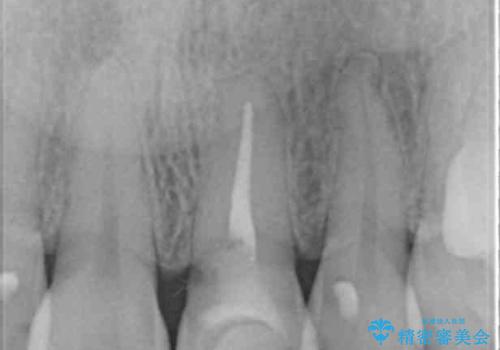

- 10年以上前に神経を取り除いた前歯の変色が気になるとのことで来院された患者様です。

レントゲン写真より、歯根の炎症が認められなかったため、ファイバーコアによる土台築製後、オールセラミッククラウンにて補綴することとしました。